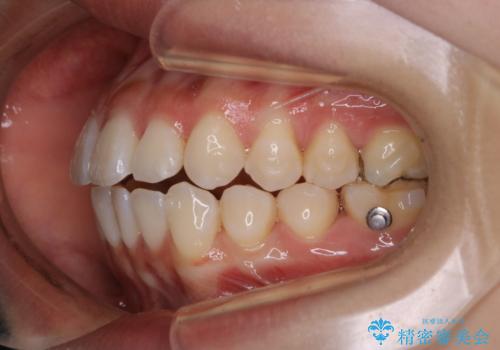

前歯で噛めない:オープンバイト(開咬)を非抜歯インビザラインで治療

- インビザラインFULL

- 1年3ヶ月

オープンバイトの方への治療は、通常抜歯を行いワイヤーによる矯正治療を行うことが多いですが、今回はインビザラインの特性を生かし、非抜歯にて綺麗な歯並びを作ることが出来ました。

舌癖がある方は、歯を内側から押し出す力が日常的に働くため、矯正治療後も歯と歯の隙間が開いてしまうなどの後戻りのリスクが高いことが知られています。舌の正しいポジショニングやお口周りの筋肉のトレーニングを行うことで後戻りのリスクを減らすことが可能です。